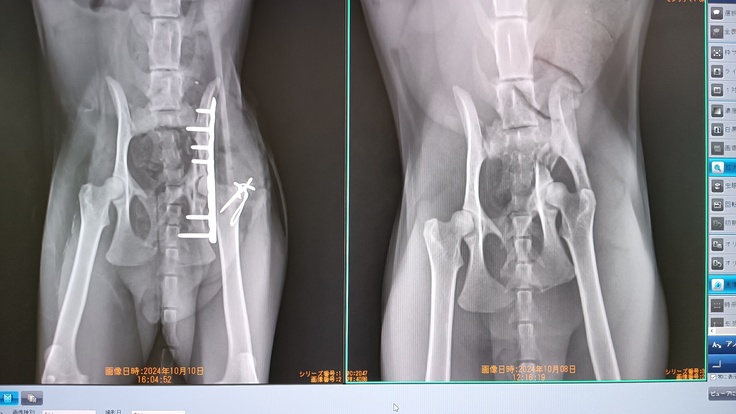

16時頃連絡があり手術は成功しました。

小柄な成猫なこと、神経が骨折で圧迫されていたことがあり再手術になるかもしれないこと、1週間入院をして10/17日の

レントゲンで判断するとのこと。

手術は無事成功して10/18の退院日まで再手術はないとのこと(17日退院でしたが時間外のため翌日に変更)

今後の治療としては2,3か月後まで週一で通院

その都度必要ならばレントゲン(暴れてしまうと毎度鎮静剤)

釘のようなボルトは今後取るかもしれない。(動いて皮膚を刺激してしまう場合)プレートはそのまま。